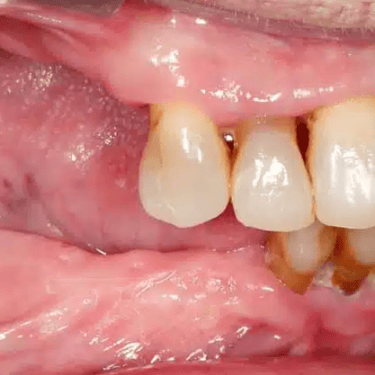

Pérdida de múltiples dientes

La pérdida de múltiples dientes es la ausencia de varios dientes que puede ser resultado de caries, enfermedades periodontales o traumatismos.

Los pacientes notan varios espacios vacíos en su boca, lo que afecta su capacidad para masticar y hablar adecuadamente.

El tratamiento incluye la colocación de varios implantes dentales para restaurar la función y la estética.